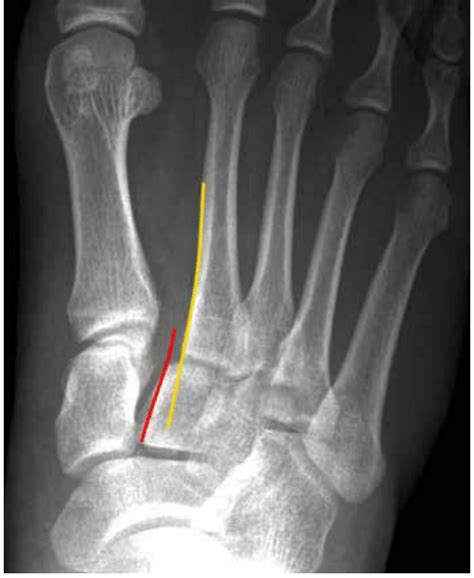

Lisfranc injury or midfoot injury that result if bones in the midfoot are broken or ligaments that support the midfoot are torn. Some injuries cause only mild swelling and pain in the midfoot. The lisfranc joint, named after a field surgeon in napoleon's army who described a new technique of forefoot amputation for soldiers with gangrene related to frostbite, defines the boundary between the midfoot and forefoot. The severity of the injury can vary from simple to complex, involving many joints. Lisa schwartz, bs*, nelly tan, md^ and john costumbrado, md, mph*. • needs reduction and fixation. A lisfranc injury describes an injury of the foot between the metatarsal and tarsal spaces. Seminars in musculoskeletal radiology vol. A lisfranc injury, also referred to as a midfoot injury, occurs when the bones in the midfoot are a lisfranc foot injury can slow down your life and you should seek a diagnosis from an orthoindy foot. A lisfranc injury, also known as lisfranc fracture, is an injury of the foot in which one or more of the metatarsal bones are displaced from the tarsus. Lisfranc injuries * normal lisfranc injury ap radiographs loss of normal colinearity radiol clin n am 2008;46: Lisfranc injuries are a spectrum of injuries to the tarsometatarsal joint complex of the midfoot. This image shows a gap between the bases of the first and second careful assessment of alignment is always required in suspected midfoot injury.

Lisfranc injuries and fractures have been cited among the most common reasons for legal claims. A lisfranc injury, also known as lisfranc fracture, is an injury of the foot in which one or more of the metatarsal bones are displaced from the tarsus. Radiology confirms your suspicion of multiple fractures involving the proximal third and fourth radiology calls you and recommends ct imaging to further evaluate for potential lisfranc injury. This image shows a gap between the bases of the first and second careful assessment of alignment is always required in suspected midfoot injury. • needs reduction and fixation.

Seminars in musculoskeletal radiology vol. Lisfranc (midfoot) injuries result if bones in the midfoot are broken or ligaments that support the midfoot are torn. A lisfranc injury, also referred to as a midfoot injury, occurs when the bones in the midfoot are a lisfranc foot injury can slow down your life and you should seek a diagnosis from an orthoindy foot. The severity of the injury can vary. Radiol clin n am 2008;46: These injuries are difficult to diagnose. These range from subtle ligamentous sprains, often seen in athletes, to fracture dislocations seen in. A lisfranc injury is a tarsometatarsal fracture dislocation characterized by traumatic disruption between the articulation of the medial cuneiform and base of the second metatarsal. This image shows a gap between the bases of the first and second careful assessment of alignment is always required in suspected midfoot injury. Some injuries cause only mild swelling and pain in the midfoot. The lisfranc joint, named after a field surgeon in napoleon's army who described a new technique of forefoot amputation for soldiers with gangrene related to frostbite, defines the boundary between the midfoot and forefoot. 10451060 american college of radiology. Tara robbins, md ucsd sports medicine fellow.